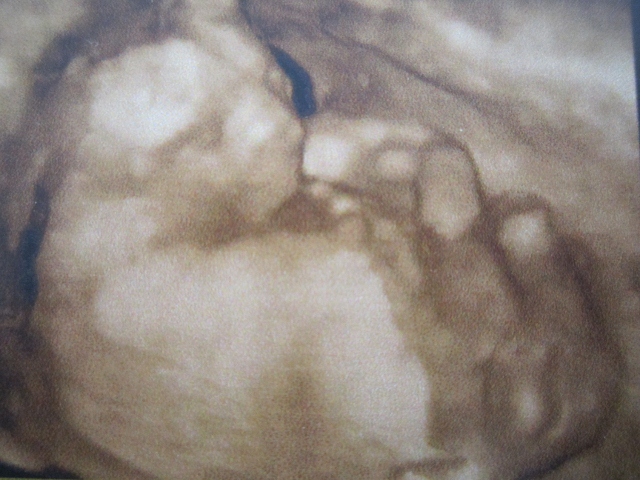

And a 3D picture

I can't see a nub sorry. But in the 3D picture, the face is clearly shown, then down there, there is something underneath the leg, are those the balls? Or I'm seeing wrong? But if what I'm seeing are the balls....I think they're too big for a baby...sorry I'm not of much help :(

Thank you dreamingpink! I think what you are seeing is a part of the leg (if that is what you mean).